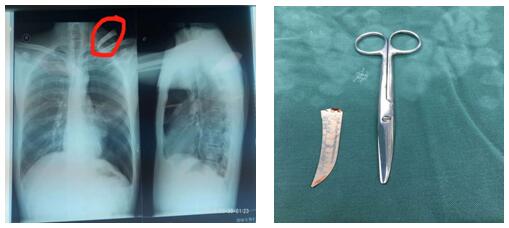

患者左頸根部可見一長(zhǎng)約2cm傷口,邊緣整齊,內(nèi)插入刀片斷端出血不止。左頸根部刀刺傷常常會(huì)損傷頸胸部大血管導(dǎo)致大出血危及生命、同時(shí)會(huì)造成開放性氣胸危及生命,病情非常危急,需行急診開胸探查術(shù)。苗主任與李偉主治醫(yī)師、李仁栓主治醫(yī)師立即制定了手術(shù)方案。1:40分患者被送進(jìn)手術(shù)室,在全麻下行胸腔鏡探查楔形切除、肋間血管縫合,胸壁傷口清創(chuàng)術(shù)。手術(shù)緊張有序地進(jìn)行。凌晨4點(diǎn)鐘患者安全返回病房,手術(shù)順利完成。從患者頸部取出的刀片長(zhǎng)約10cm 左右。